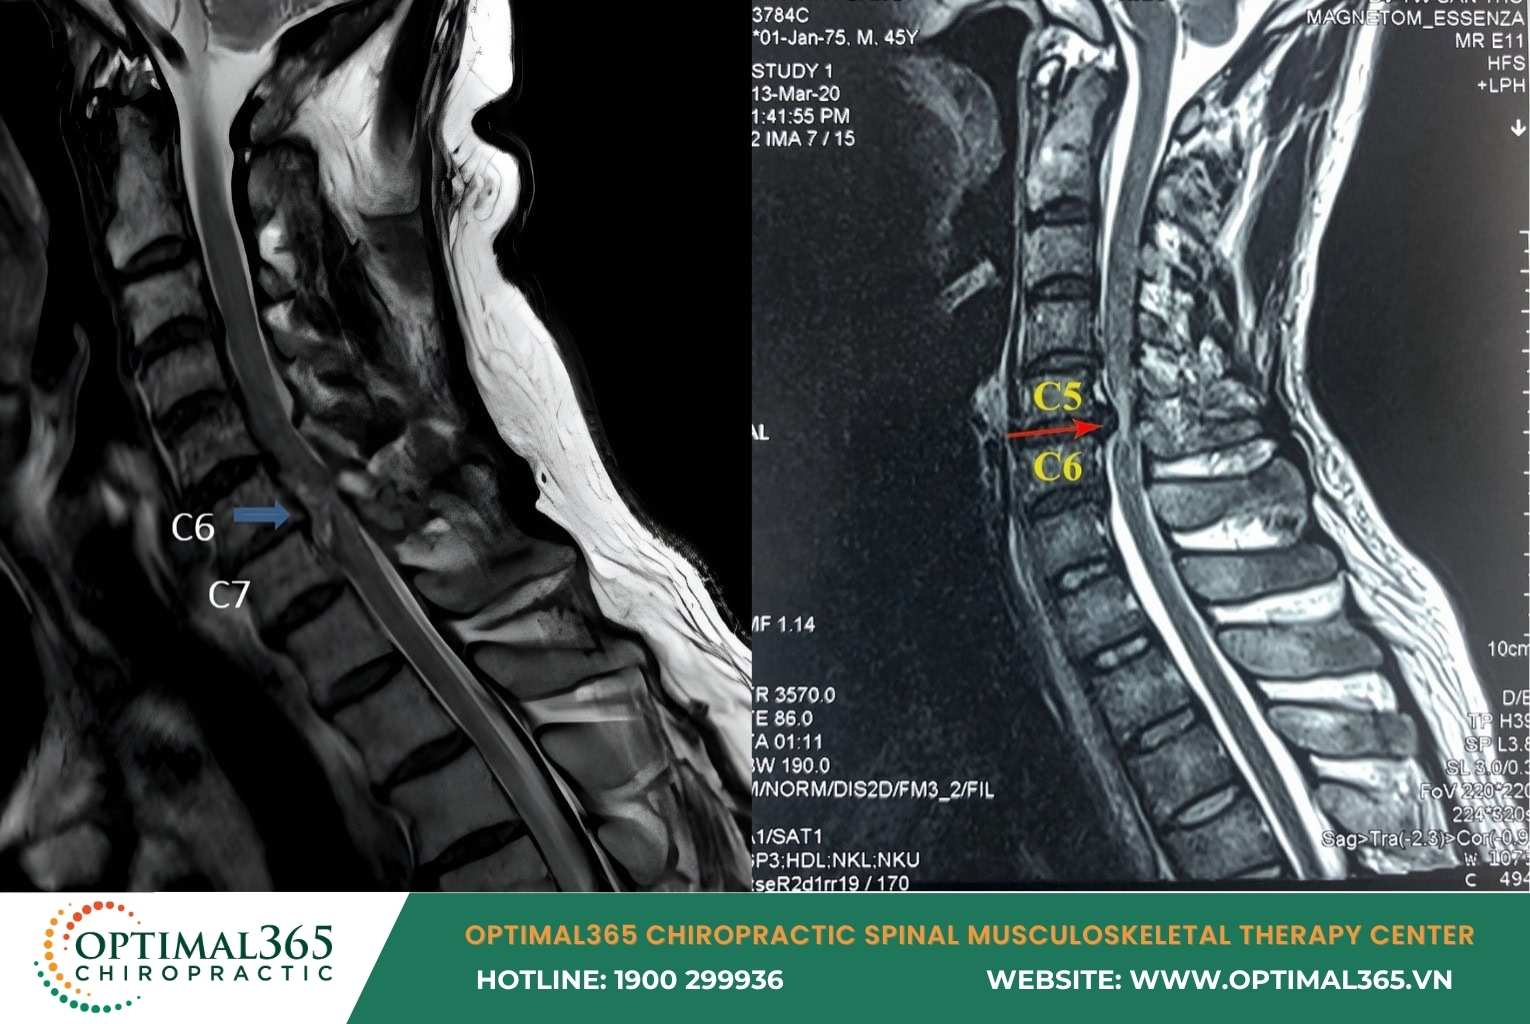

In subclinical cases, cervical herniated disc symptoms are detected via MRI showing: Disc herniating anteriorly or posteriorly, nucleus pulposus displaced, spinal structure changes, and compression on nerve roots or spinal cord.